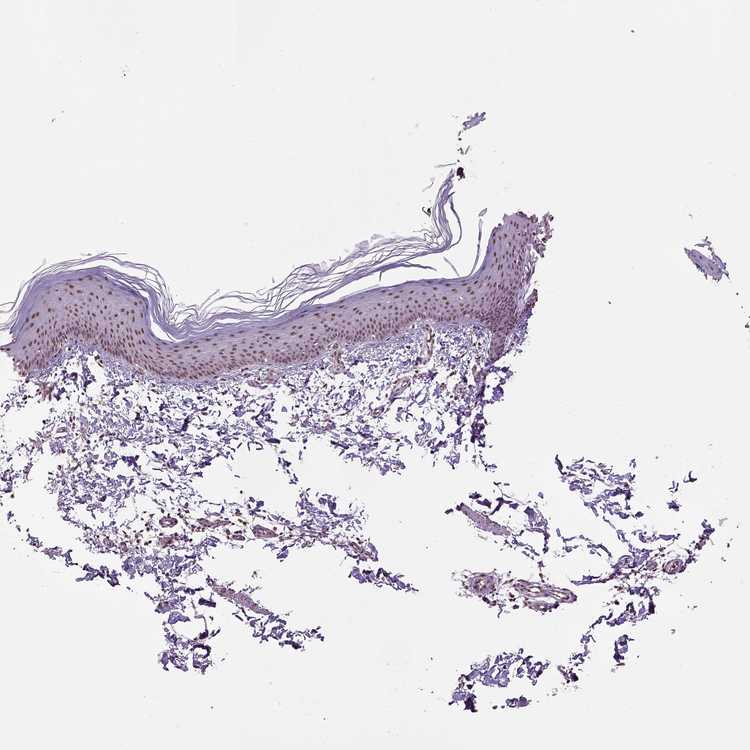

SKIN 1 - Antibody stainingi

Antibody staining in the annotated cell types in the current human tissue is reported as not detected, low, medium, or high, based on conventional immunohistochemistry profiling in selected tissues. This score is based on the combination of the staining intensity and fraction of stained cells.

Each image is clickable and will lead to virtual microscopy that enables deeper exploration of all samples and also displays staining intensity scores, fraction scores and subcellular localization as well as patient and tissue information for each sample.

Antibody HPA034873Antibody HPA034874Antibody HPA065335

Langerhans LowMediumMedium

Fibroblasts MediumMediumMedium

Keratinocytes MediumHighMedium

Melanocytes MediumMediumMedium

SKIN 2 - Antibody stainingi

Epidermal cells MediumMediumMedium